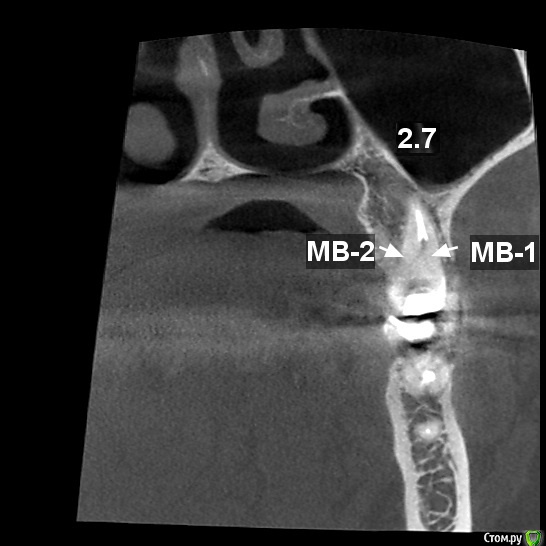

tatsiana.ma Опубликовано 23 ноября, 2016 Автор Поделиться Опубликовано 23 ноября, 2016 (изменено) 17-го числа без анастезии убирали метапекс. Два канала нормально, а в мезиально-щечном канале при прохождении файлами последней трети длины канала - возникает резкая боль, обильное слюноотделение. Боль не в самой верхушке, а когда до апекса остается еще несколько мм. И прохождение этих нескольких мм - пытка. Заложили апексдент.Вечером и по ночам зуб перестал ныть, по днем небольшая ноющая и иногда распирающая боль присутствует. В первые два дня после закладки апексдента отечность на щеке частично спала, но потом процесс остановился. Что может давать такую резкую боль?На КТ как раз над мезиально-щечным корнем есть странная вещь, см. фото. То ли такое разрежение костной ткани под кортикальной пластиной (стоматолог), то ли уплотнение самой кортикальной пластины в этом участке (рентгенолог). Ваше мнение что это над МЩК? это может быть связано с болевыми ощущениями при прохождении мщ канала? Изменено 23 ноября, 2016 пользователем tatsiana.ma Ссылка на комментарий

tatsiana.ma Опубликовано 29 ноября, 2016 Автор Поделиться Опубликовано 29 ноября, 2016 Плиииииииииииииз, очень нужна помощь знатоков.Сегодня опять была у стоматолога. Искали четвертый канал в зубе, в МЩК 2 канала.По данным КТ и скрину рентгенолога (см.рис1) в этом корне отдельные входы каналов с дальнейшим их слиянием в апикальной части.В итоге полость зуба раскрыта максимально, входа не видно и не чувствуется (см.рис 2). Затем расширено устье мщк, поиск шел внутри основного канала. На глубине ~5мм от входа найдена болезненная точка, файл за нее цепляется. Предположительно это вход в дополнительный канал, но пройти внутрь за эту точку дальше, чем на 2 мм не получается. Закрыли зуб лекарством, следующий прием через неделю.Может ли быть такая конфигурация, что в глубине основного канала открывается вход в канал дополнительный? или это вероятность что выходим не в канал, а на перфорацию? Ссылка на комментарий

DmitrySH Опубликовано 29 ноября, 2016 Поделиться Опубликовано 29 ноября, 2016 Извините, на КТ отмечены не каналы. Ссылка на комментарий

tatsiana.ma Опубликовано 29 ноября, 2016 Автор Поделиться Опубликовано 29 ноября, 2016 (изменено) Извините, на КТ отмечены не каналы. Вот этого я и боялась. Но этот срез сделан из КТ рентгенологом и она же ставила отметки на картинке и писала расшифровку. Что же она указала?.. Уже и зуб распахали весь, что дальше некуда((( Но боль при прохождении МЩК есть, вот сегодня эту точку боли нашли, но дальше чем 2 мм вглубь пройти пока не получается. То ли все-таки есть какой-то дополнительный канал (склерозирован?), то ли ковыряем неизвестно что. Я боюсь, чтобы не перфорировали стенку.На первоначальном снимке до депульпирования от середины корня к апексу вроде похоже на два канала в мщк. Да? Подскажите, пожалуйста. Изменено 29 ноября, 2016 пользователем tatsiana.ma Ссылка на комментарий

DmitrySH Опубликовано 29 ноября, 2016 Поделиться Опубликовано 29 ноября, 2016 На этом срезе кт четко видны только 3 канала. Что указано рентгенологом на прошлом срезе, затрудняюсь сказать. Выкладывайте весь диск с КТ Ссылка на комментарий

DmitrySH Опубликовано 30 ноября, 2016 Поделиться Опубликовано 30 ноября, 2016 http://s020.radikal.ru/i716/1611/5d/da2a5947af14.jpg с первого диска, все хорошо видно. 1 канал в переднем корне, в середине делится на 2, у апекса сходятся. как-то так 2 Ссылка на комментарий